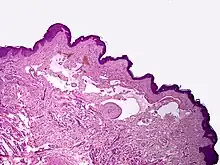

Microscopically, the vesicles in lymphangioma circumscriptum are greatly dilated lymph channels that cause the papillary dermis to expand. They may be associated with acanthosis and hyperkeratosis. There are many channels in the upper dermis which often extend to the subcutis (the deeper layer of the dermis, containing mostly fat and connective tissue). The deeper vessels have large calibers with thick walls which contain smooth muscle. The lumen is filled with lymphatic fluid, but often contains red blood cells, lymphocytes, macrophages, and neutrophils. The channels are lined with flat endothelial cells. The interstitium has many lymphoid cells and shows evidence of fibroplasia (the formation of fibrous tissue). Nodules (A small mass of tissue or aggregation of cells) in cavernous lymphangioma are large, irregular channels in the reticular dermis and subcutaneous tissue that are lined by a single layer of endothelial cells. Also an incomplete layer of smooth muscle also lines the walls of these channels. The stroma consists of loose connective tissue with a lot of inflammatory cells. These tumors usually penetrate muscle. Cystic hygroma is indistinguishable from cavernous lymphangiomas on histology.[4]

Lymphangiomas have traditionally been classified into three subtypes: capillary and cavernous lymphangiomas and cystic hygroma. This classification is based on their microscopic characteristics. A fourth subtype, the hemangiolymphangioma is also recognized.[9]

- Capillary lymphangiomas are composed of small, capillary-sized lymphatic vessels and are characteristically located in the epidermis.